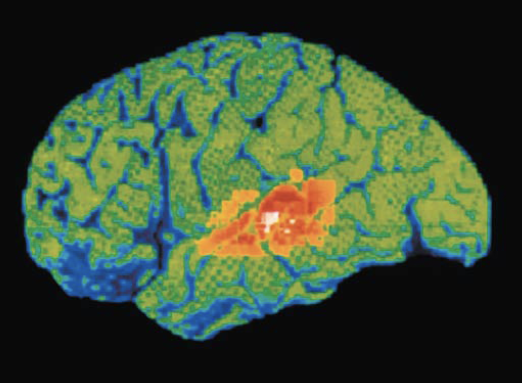

Functional imaging (PET and MRI) of brain show specific motor and sensory functions are located in discrete cortical areas called domains

Cerebral Cortex

Motor areas

Located in frontal lobe, motor areas act to control voluntary movement

Primary (somatic) motor cortex

Located in precentral gyrus of frontal lobe

Pyramidal cells: large neurons that allow conscious control of precise, skilled, skeletal muscle movements

Pyramidal (corticospinal) tracts: formed from long axons that project down spinal cord

Somatotopy: all muscles of body can be mapped to area on primary motor cortex